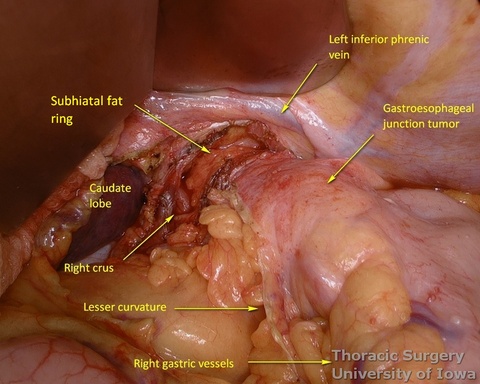

- Subhiatal fat ring is exposed after division of the lower leaflet of the phrenoesophageal ligament

- The abdominal esophagus, periesophageal fat, and nodes are dissected and encircled with a Penrose drain for retraction.

- The mediastinum is entered with the combination of sharp and blunt dissection. Note that postradiation adhesions become denser 4-6 weeks after neoadjuvant treatment.

- Once the mediastinum entered, the manual palpation through the hiatus is performed to assess mobility of the esophagus. Tumor is “rocked” from side to side to make sure it is not adherent to the aorta, prevertebral fascia, or mediastinal structures, thus assuring the feasibility of transhiatal approach or the need to perform transthoracic dissection. This should also be planned based on preoperative imaging.

- Once the stomach is mobilized and reflected anteriorly, the left gastric vascular pedicle is identified and dissected close to the origin for adequate lymphadenectomy. Care is taken to not injure splenic artery and pancreas.

- Postradiation adhesions may be dense.

- Left gastric vessels are divided with an endoscopic linear cutting stapler proximally, including all adjacent lymph nodes in the specimen.